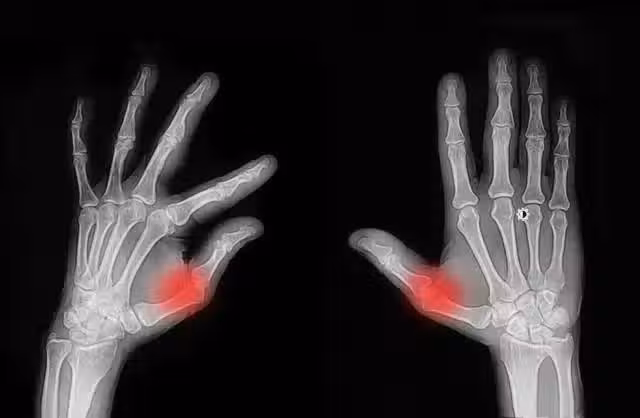

經常掰手指,老了會得關節炎?這樣響沒事,又響又痛可能是這些病